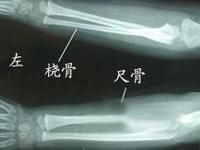

根據臨床表現和X線檢查可作出診斷。Wilkie將該病分為兩種類型:I型尺橈骨融合中,尺橈骨的髓腔貫通。橈骨近端畸形,與尺骨有數厘米的融合,橈骨比尺骨長、粗,其骨幹向前彎曲。Ⅱ型融合,橈骨基本正常,但橈骨近端前脫位或後脫位,並與尺骨幹近端融合。融合不十分廣泛,也不如I型那么緊密,Wilkie報導Ⅱ型畸形常發生於單側,有時合併多指、缺指或並指等其他畸形。